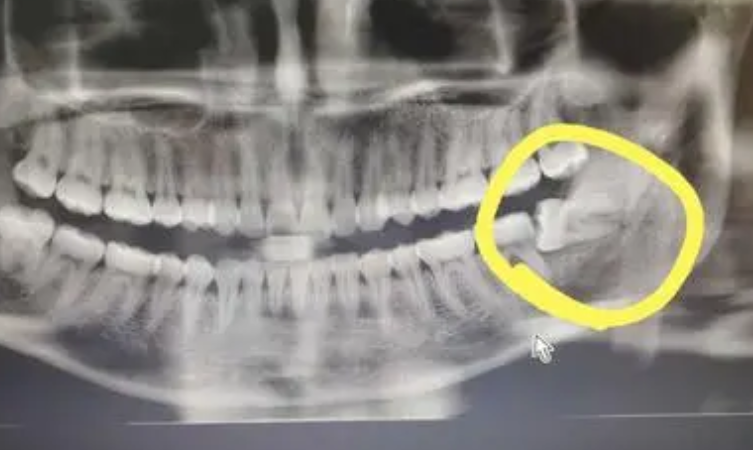

1、拔阻生智齒:拔智齒是這家醫(yī)院很不錯的項目之一,醫(yī)生在做阻生和埋伏智齒拔除的時候,手法都比較細膩,形成的創(chuàng)口比較小,術后恢復的會比較快。

我的口腔當中左側下面的智齒經常會導致我牙齦疼痛,后來我才知道,這是因為這個牙齒有埋伏現(xiàn)象,為了能夠使這顆牙齒帶來的疼痛快點得到消除,我在南方醫(yī)科大學珠江醫(yī)院的牙科做了拔智齒的手術。

拔智齒過程中

在拔智齒的時候,醫(yī)生給我使用了麻藥,所以拔智齒的時候雖然有點疼痛感,但并不是特別的嚴重。工作手術手法比較輕柔,做完之后創(chuàng)口恢復的也挺快的,不到兩周的時候就已經看上去恢復如初了,不過醫(yī)生告訴我還需要做好護理,要在一個月之后才能夠真的恢復好。

拔智齒之后

現(xiàn)在我拔完智齒已經兩個多月了,果然沒有了這顆智齒之后,我的牙齒再也沒有出現(xiàn)發(fā)炎疼痛的癥狀,而且口腔的整體健康度都比較好。